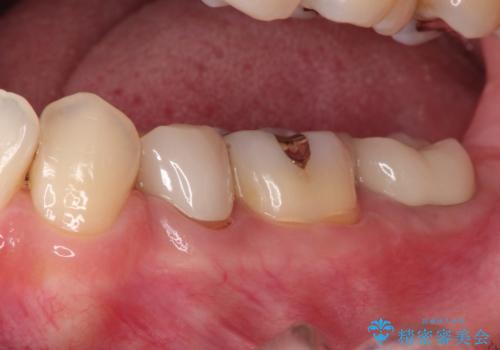

奥歯が痛い。根管治療からセラミッククラウン

- 奥歯が痛いことを主訴に来院されました。

レントゲンにて根尖病変を認め、根管治療を行ったのちセラミッククラウンにて修復しました。根管治療は川島先生に依頼。

咬合力が強くかかる部分には欠けるリスクのほとんどない金属を用いることが最良ですが審美性に劣ります。

今回は白い材料での修復を希望されたため、セラミッククラウンにて治療を行いました。